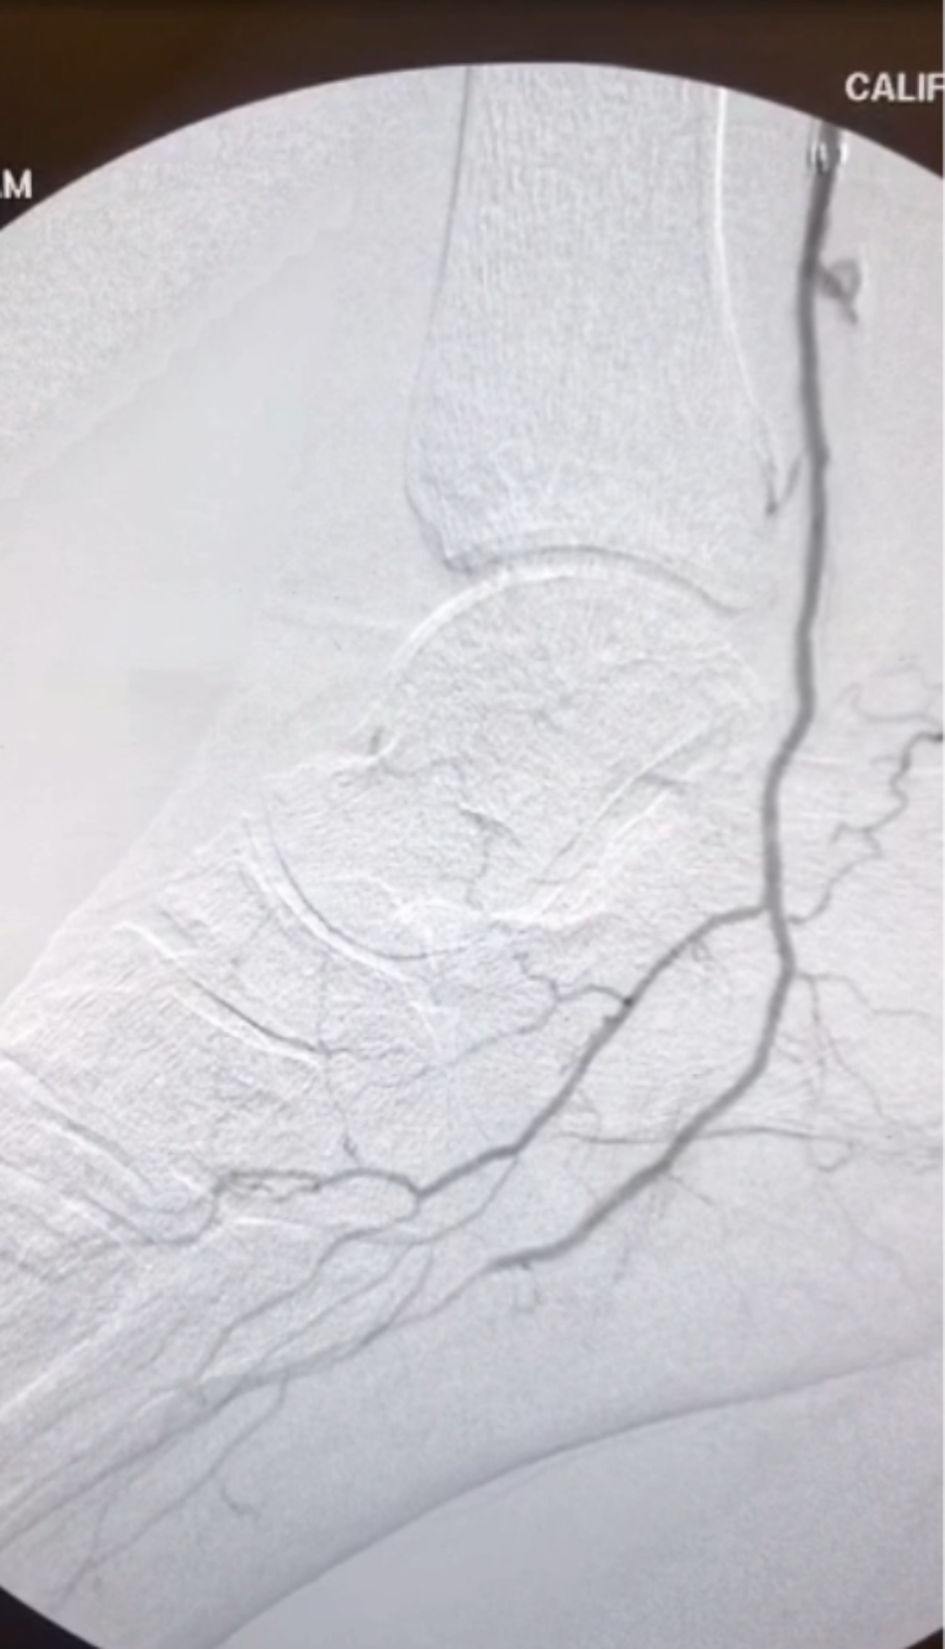

A 7-Fr sheath was inserted antegrade into the CFA and a snare was inserted into the bypass graft. A 6-Fr pedal sheath was inserted retrograde into the distal posterior tibial artery to allow for stable device delivery and retrieval during tract creation. The vessel diameter was adequate to accommodate this size without compromise. Using the double-gunsight technique - a fluoroscopically guided method in which two snares are aligned to target a percutaneous puncture tract - a micropuncture needle was passed through both snares to establish through-and-through access. Distal angiography confirmed a patent plantar arch with in-line flow through the lateral plantar artery and digital branches. A Command 0.018-in wire was flossed through and snared from both ends, enabling angioplasty of the tract with a 4 mm balloon (Fig. 3). A 5 × 100-mm Viabahn stent graft was deployed to bridge the bypass graft to the PTA. A 4-mm balloon was inflated in the bypass portion. The tibial sheath was removed, and through antegrade access, a Command 0.014-in wire was placed into the lateral plantar artery, followed by angioplasty of the PTA with a 2.5-mm balloon and the plantar artery with a 2.0-mm balloon. Post-revision angiography revealed greatly improved blood flow into the arterial plantar arch (Fig. 4). The patient showed signs of healing. At two months post-revision, the patient had avoided amputation and no longer required medication for pain control.

Click for large image

Figure 4. Post-revision angiography showed improved blood flow to the arterial plantar arch.